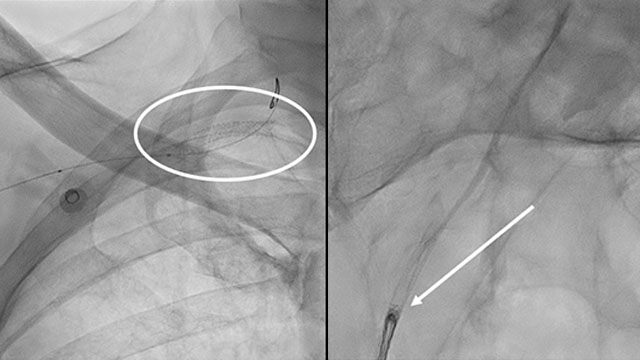

Case Study Coughing Concomitant With Stent Deployment Leading To Embolisation Of A Right Coronary Artery Stent